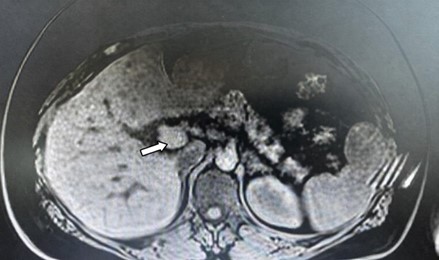

A 40-year-old female (height 1.55 m, body weight 105 kg, and BMI 43.75 kg/m²) prese-nted with hypertension, hypokalemia, fatigue, muscle cramps, and generalizedweakness. A computed tomography (CT) scan revealed a left adrenal adenoma (Figure 1), and she was planned for a left-sided laparoscopic adrenalectomy.

Figure 1. Patient’s computed tomography (CT) scan demonstrating a left adrenal adenoma (arrow).

Abdominal ultrasonography identified hepatic steatosis, and both kidneys exhibited normal size, parenchymal thickness, and echogenicity. The right adrenal gland appeared normal, whereas a 21×15 mm lesion was noted in the left adrenal gland (Figure 1). The patient was on antihypertensive therapy including nifedipine 30 mg twice daily, doxazosin 4 mg once daily, and nebivolol 5 mg once daily. Potassium (K+) supplementation was continued with tablets containing 2 grams of potassium bicarbonate and 2.17 grams of potassium citrate, administered twice daily. She had discontinued spironolactone treatment eight months prior. Venous aldosterone sampling was unsuccessful due to technical difficulties during catheterization. The 1 mg dexamethasone suppression test showed adequate cortisol suppression. Twenty-four-hour urine meta-nephrine and normetanephrine levels were normal. Aldosterone suppression was not observed after saline infusion testing. Based on these findings, a diagnosis of primary hyperaldosteronism was made, and surgical treatment was planned.